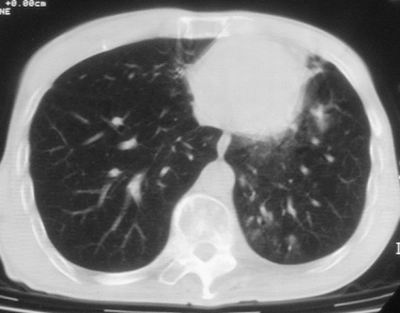

标题: CT11864:男,47岁,反复咳嗽、咯痰、咯血3年,请分析. [打印本页]

标题: CT11864:男,47岁,反复咳嗽、咯痰、咯血3年,请分析.

患者,男,47岁,反复咳嗽、咯痰、咯血3年,再发5天。痰培养未找到真菌、抗酸杆菌、癌细胞。

左肺上叶体积明显缩小,其内见多发透光区,纵隔向左侧移位,左肺下叶多发班片状病灶,边界模糊,1左肺上叶先天肺发育不全,2左肺下叶肺炎,

左肺上叶结核伴肺纤维化,纵隔移位,左肺下叶感染性病变,建议抗炎抗结核后复查,双肺气肿.

1.左肺上叶慢纤空2.左肺下叶炎症

考虑:左肺慢纤伴霉菌球形成、双肺全小叶型肺气肿。

1)考虑为:左肺上叶肺结核(空洞形成),伴左下肺感染;不排除霉菌感染可能。2)肺气肿。

左肺上叶结核伴肺纤维化空洞形成并左肺下叶感染,纵隔牵拉移位,建议作进一步检查排除左侧肺霉菌感染可能。